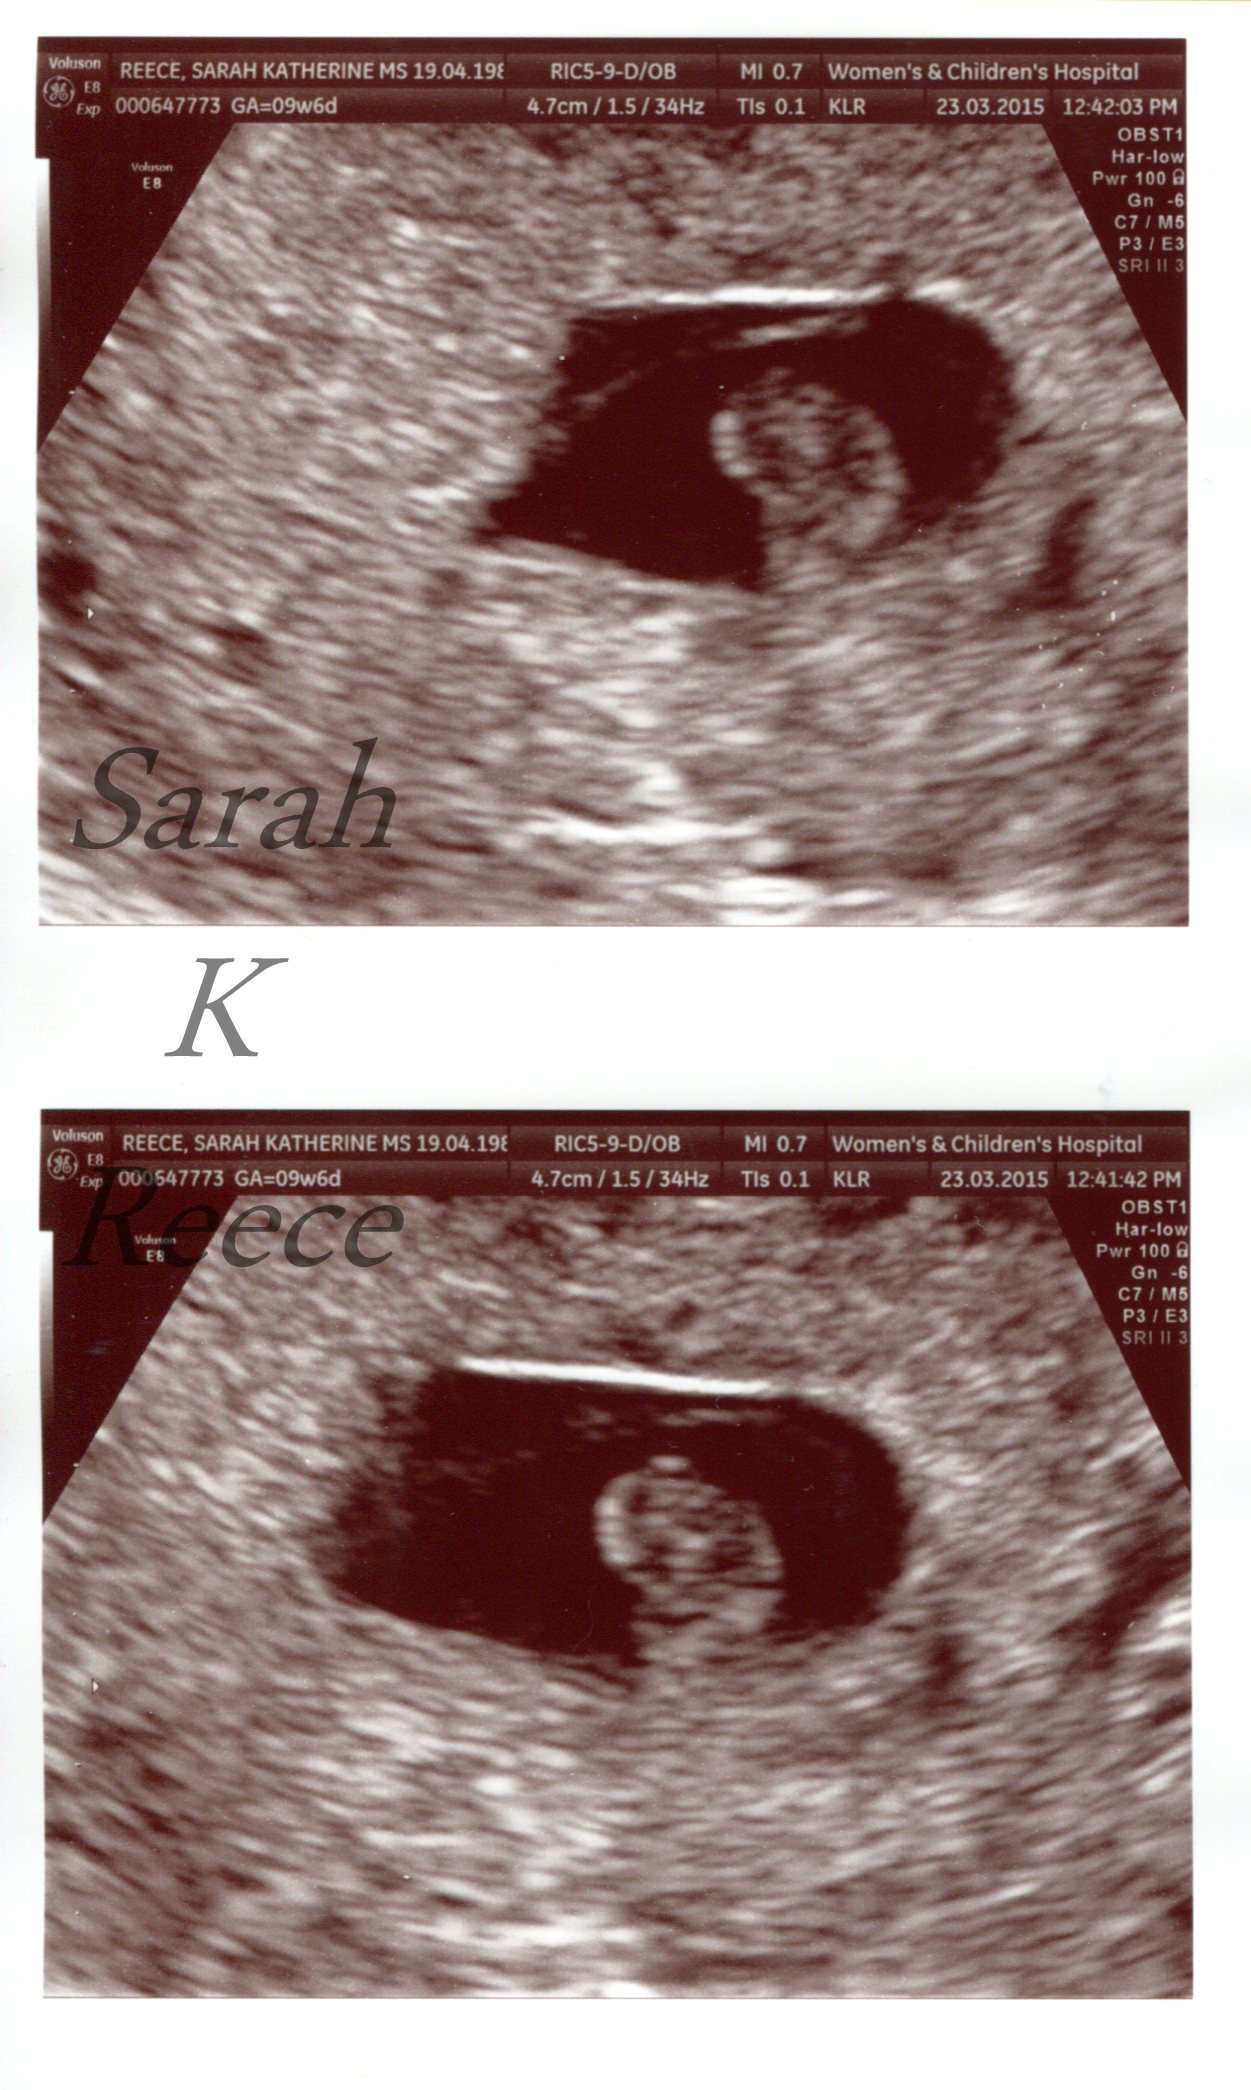

Our baby has died. There is no heartbeat, no growth, no obvious abnormalities, they’ve just died. You can see them in this last scan, all curled up, head at the top and body tucked under in the dark womb. The painful wait is over and there’s no hope left.